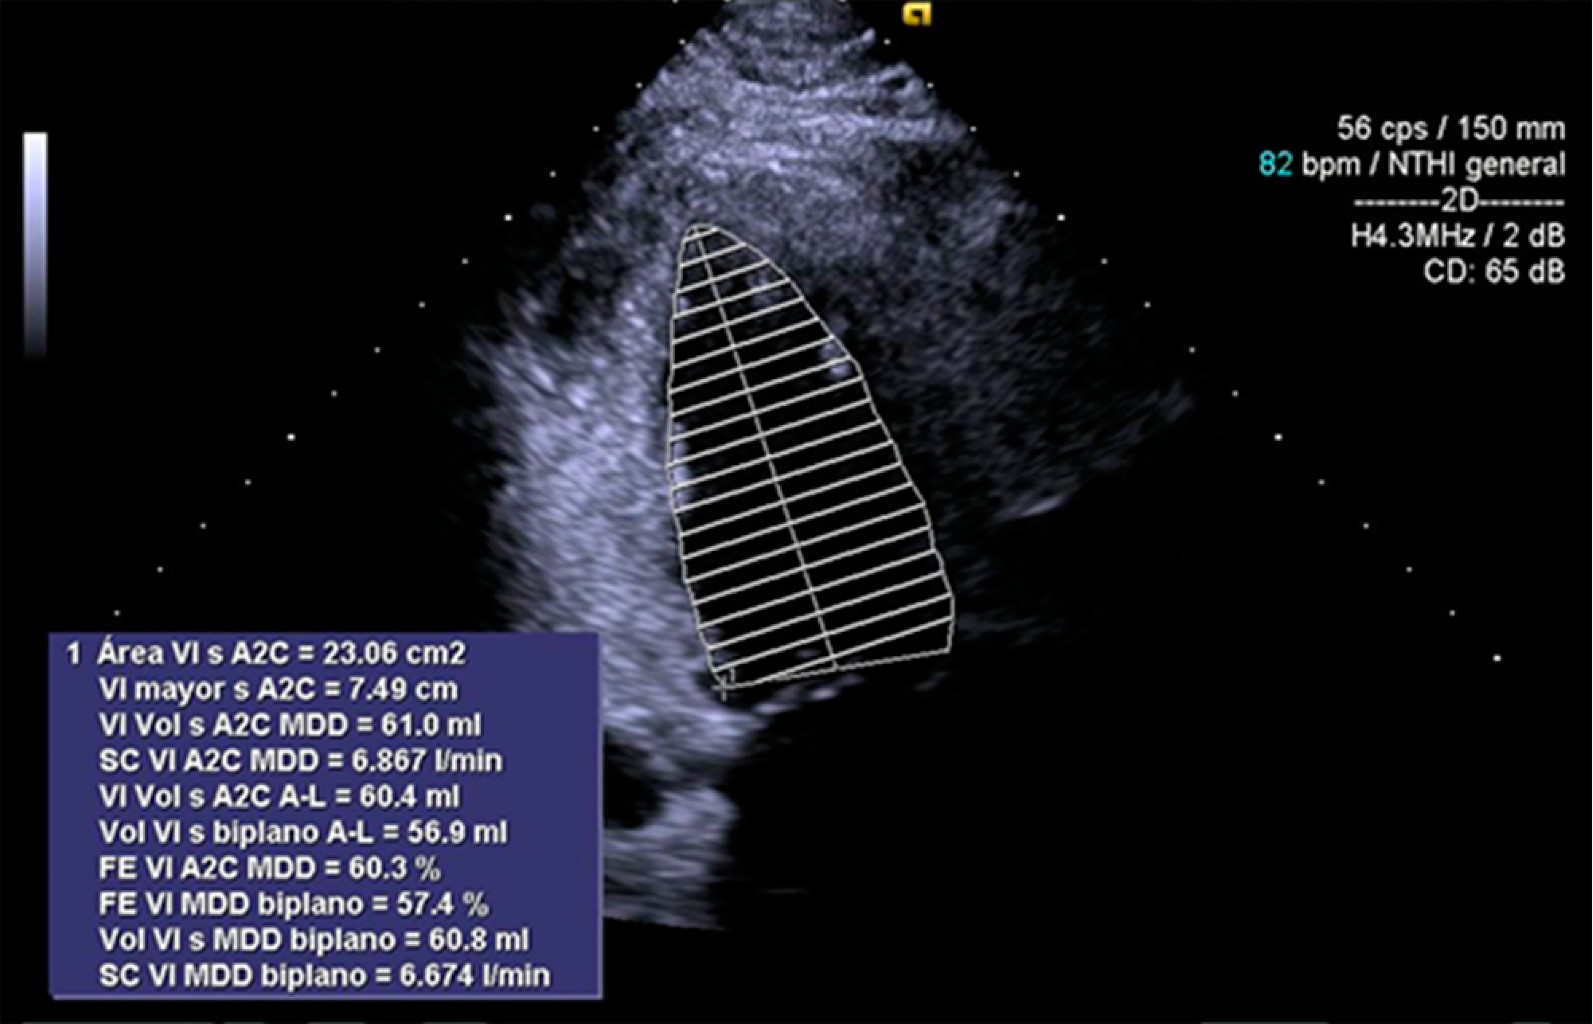

Masculino de 38 años de edad destaca dedicación a la ganadería caprina, sin uso adecuado de equipo de protección personal. Acudió al servicio de urgencias por cuadro clínico de un mes de evolución con presencia de fiebre de predominio nocturno de 39 oC, duración de tres horas, astenia, adinamia, con signos vitales tensión arterial:130/80 mmHg, frecuencia cardiaca:100 lpm, frecuencia respiratoria: 20 rpm, temperatura: 37 oC. A la exploración física sin existencia de adenopatías palpables, sin alteraciones pulmonares ni cardiacas, abdomen sin alteraciones. En la analítica hemoglobina: 17 g/dL, plaquetas: 362 × 109/L, leucocitos: 14.8 × 109/L, neutrófilos: 10.3 × 109/L, PCR SARS-CoV-2 negativa, examen general de orina y urocultivo negativos, IgG Coxiella fase I negativo, IgG Coxiella fase II positivo, IgM fase I Coxiella positivo 1,256 U/mL, IgM fase II Coxiella positivo 116,384 U/ml, radiografía simple de tórax (Figura 1), tomografía simple de tórax (Figura 2). Ecocardiograma transtorácico (Figura 3). Se inició tratamiento con paracetamol 1 gramo intravenoso cada ocho horas y doxiciclina 100 mg vía oral cada 12 horas durante dos semanas (14 días) con mejoría.

Figura 1